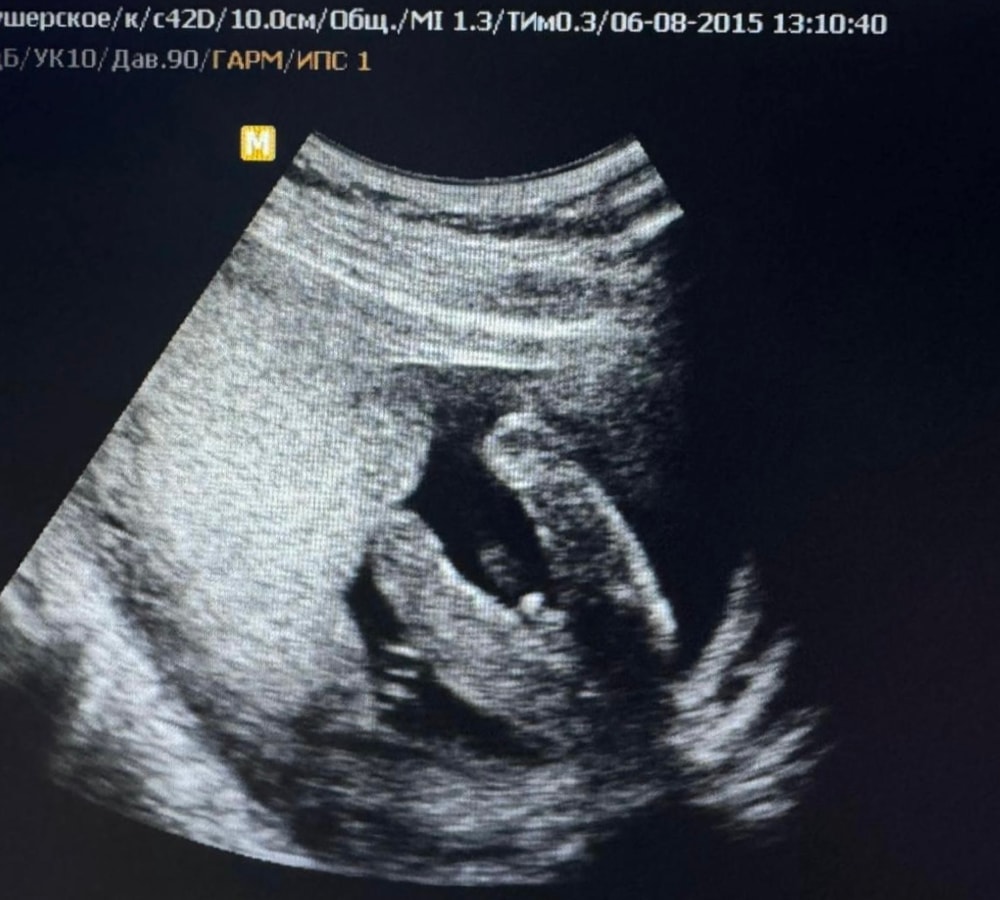

У вас еще фото не очень хорошего качества, не разобрать толком. Вот доча: Изображение А вот сын: Изображение